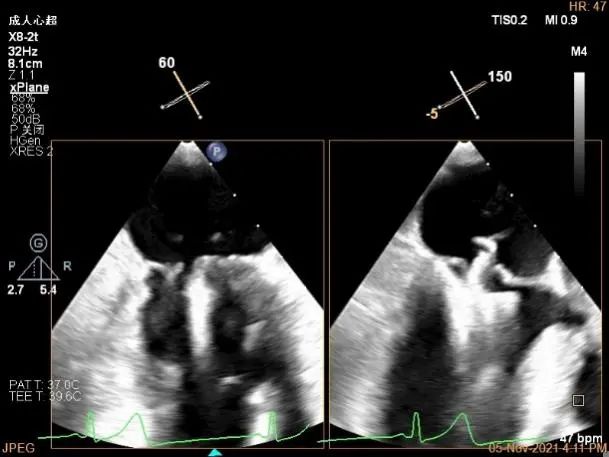

术中及术后即刻超声评估

确定房间隔穿刺点:略靠前,3D视图2点位

穿刺点高度测量:4.37cm

Multivue测量大鞘长度2.34cm

3D视图下进夹子并建立trajectory

3D视图打开夹子

3D视图下调Rotate,主要定位2区

X-plane:下夹子尝试捕获2区脱垂瓣叶

Gripper,前叶捕获长10.1mm,后叶捕获长度8.9mm

夹子逐渐夹闭后,返流量逐渐减少

夹子放置后二尖瓣口平均跨瓣压差:1mmHg

肺静脉血流频谱恢复正向

夹子脱钩后,最终仅少量残余分流

3D视图下观察二尖瓣双孔形态

3D-color:残余少量返流